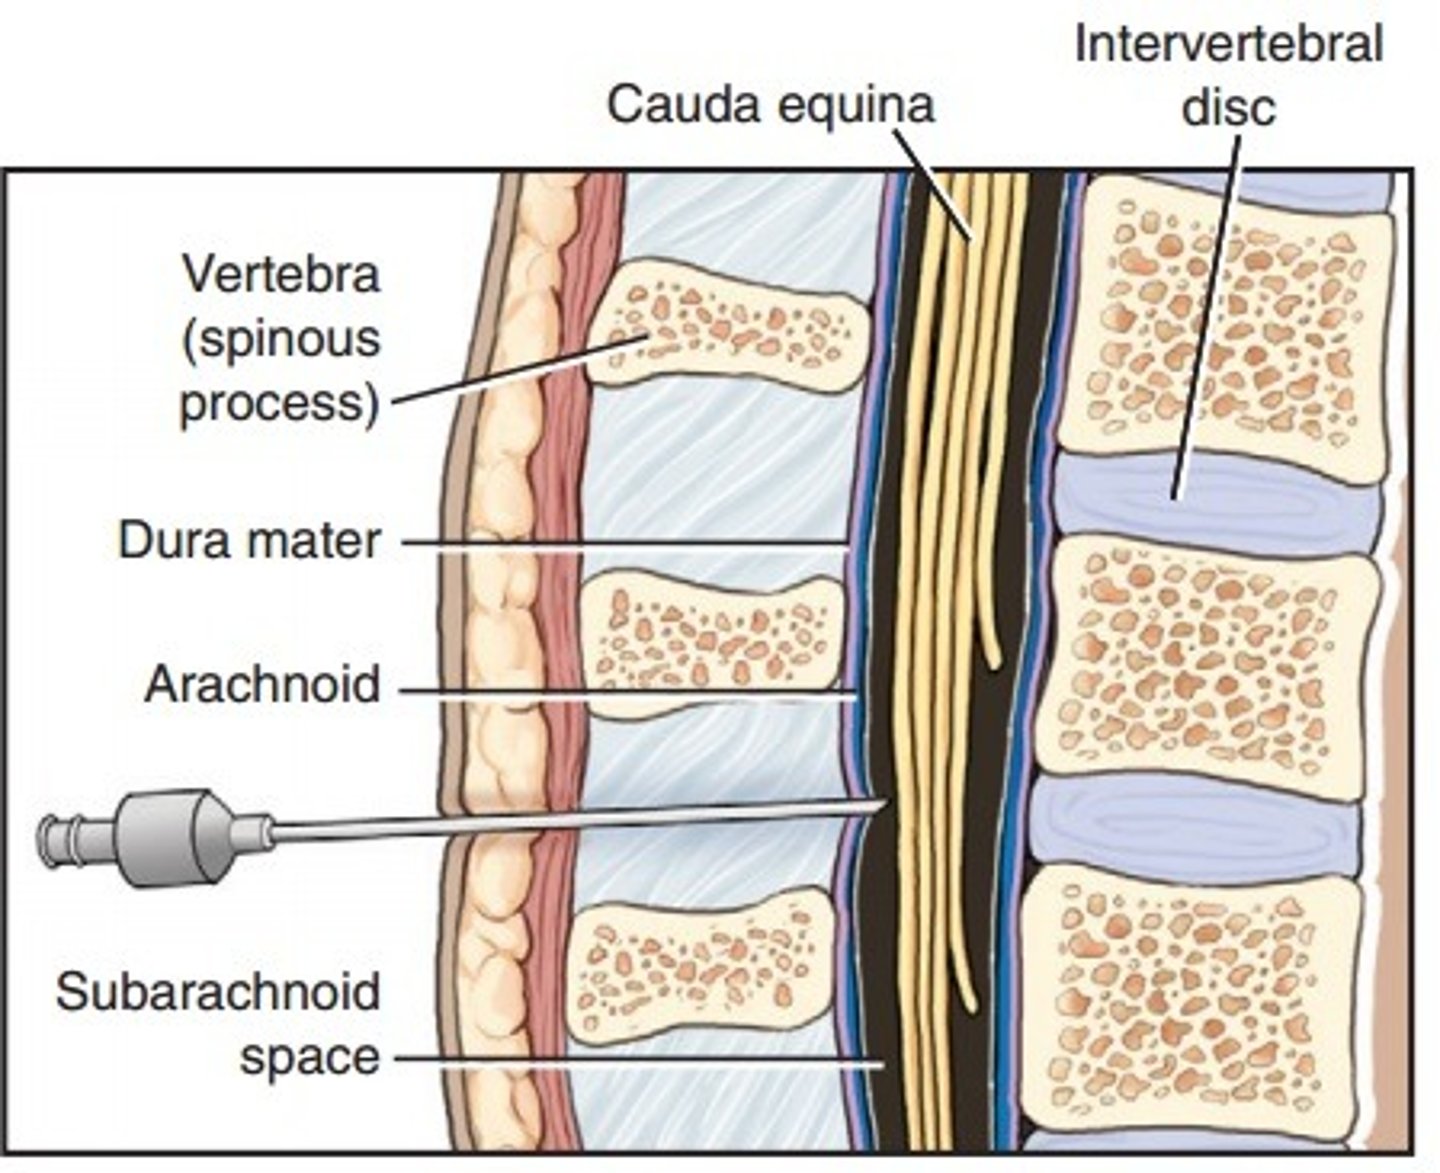

cauda equina

Nerve roots from spinal cord to lower intervertebral foramen to exit

L2 to S5 and filum terminale

spinal meninges

3 spinal meninges (Superficial to deep)

dura mater, arachnoid mater, pia mater

arachnoid mater

subarachnoid space

between arachnoid mater and pia mater

filled with cerebrospinal fluid

Lumbar puncture

Withdrawal of cerebrospinal fluid

needle inserted into subarachnoid space between two lumbar vertebrae.

Also known as spinal tap